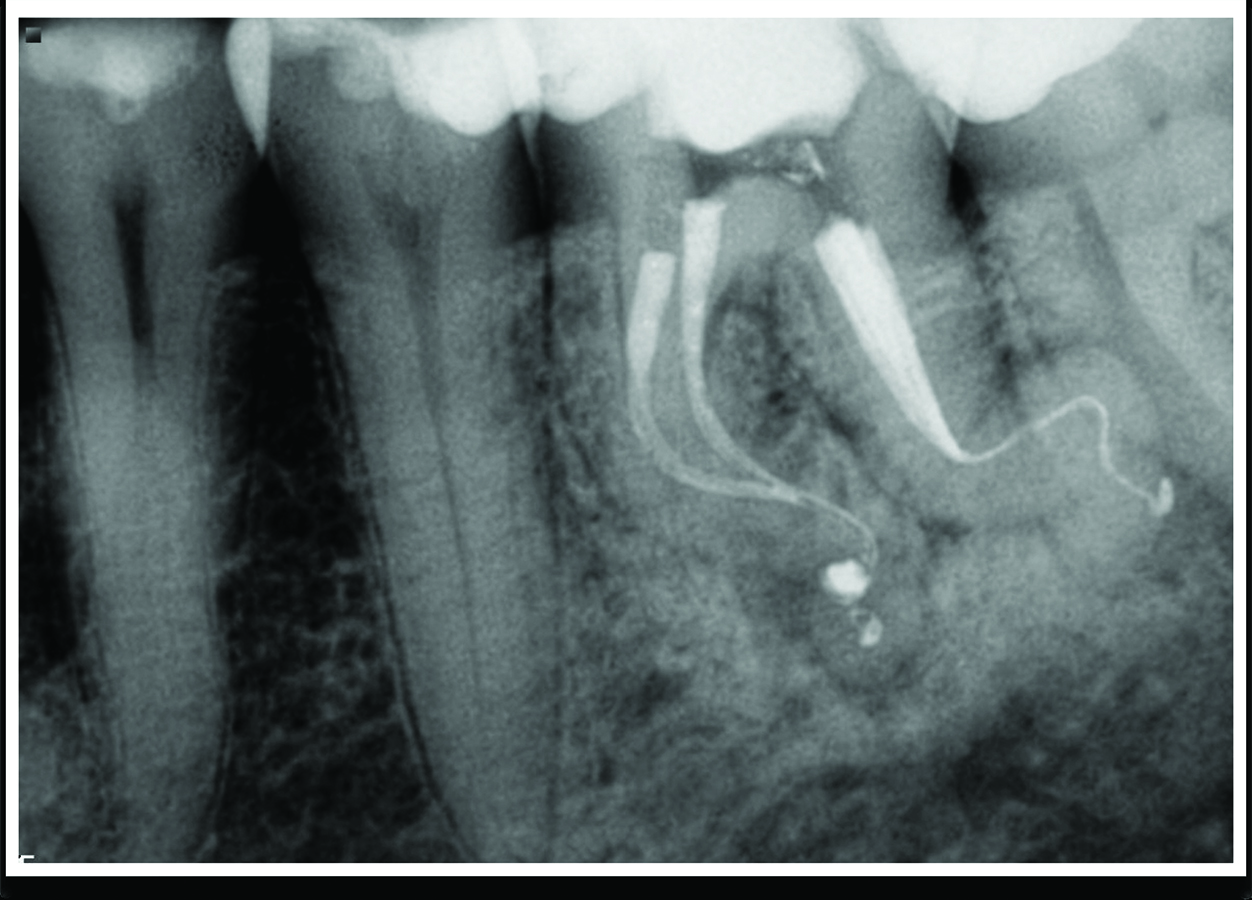

Successful Endodontic Management Using Er,CrYSGG Laser Disinfection of Laser Endodontic Disinfection Root canal treatment is the most effective and widely used method for controlling infection, promoting periapical healing, and. The efficacy of laser therapy applications in root canal disinfection with or without various irrigants protocols remains. Nd:yag laser (1064 nm) has been the most widely investigated laser for. Conventional laser use inside the root canal as an additional disinfection method;. Laboratory. Laser Endodontic Disinfection.